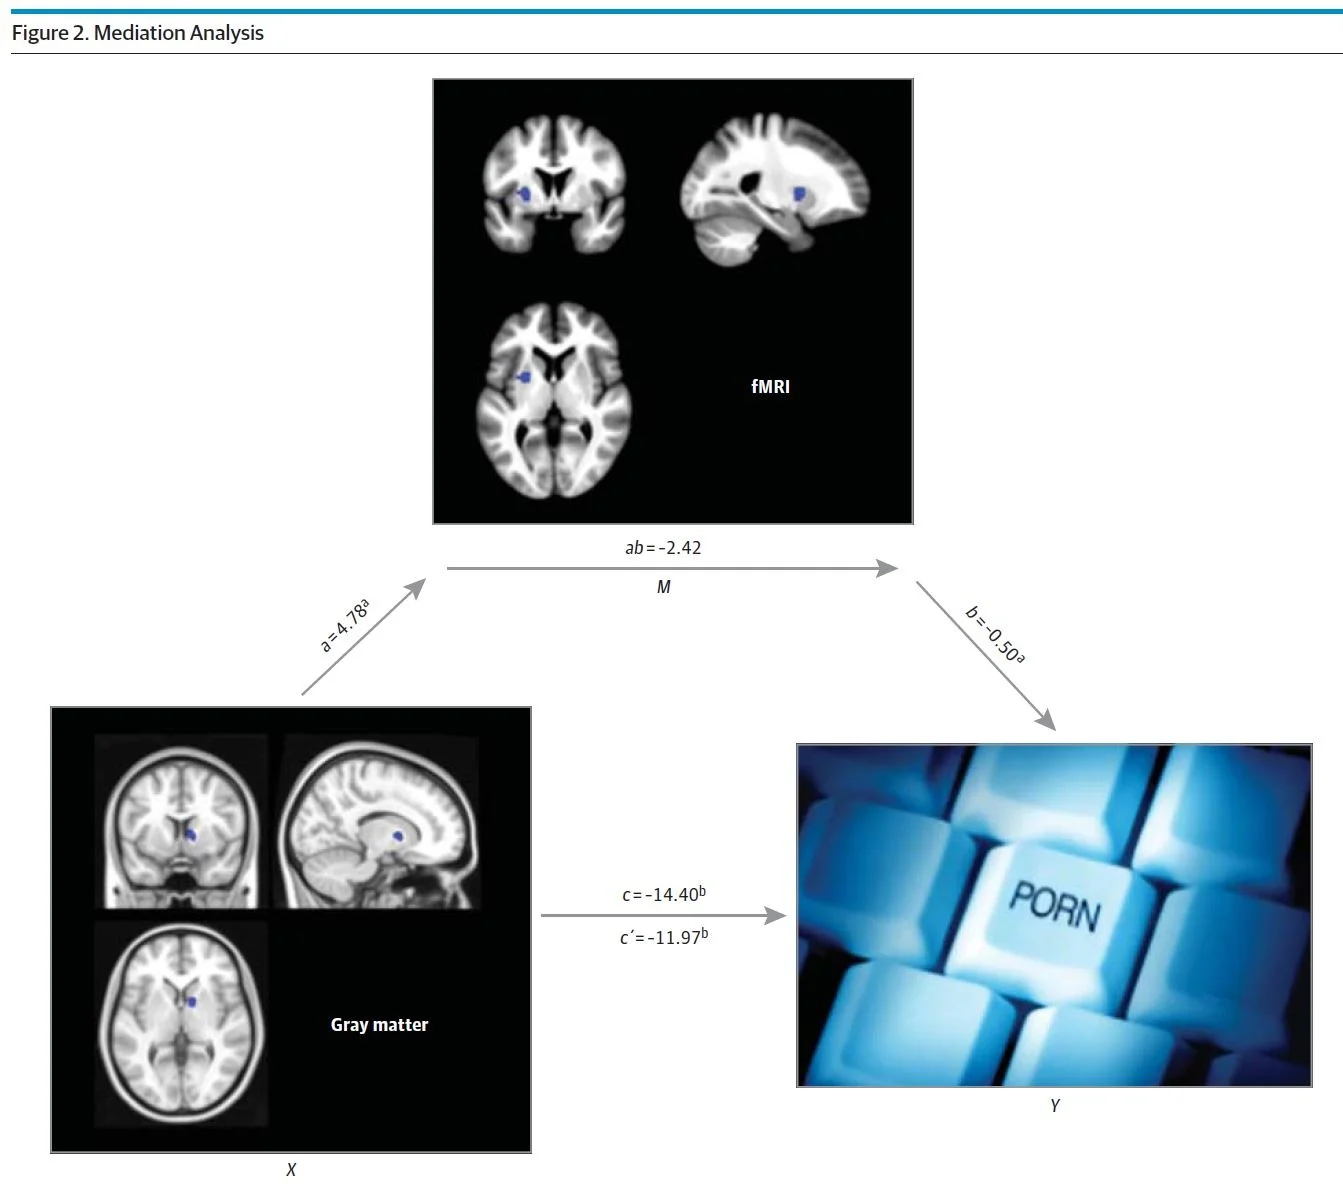

- Aju struktuur ja pornograafilise tarbimisega seotud funktsionaalne ühenduvus: aju pornograafias (2014)

Kuna sensibiliseerimine ja isud sunnivad teid pornot kasutama, viib preemiaskeemide ülestimuleerimine lokaliseeritud mässuni. Dopamiini pommitatud närvirakud ütlevad, et "piisab". Kui keegi karjub edasi, siis katate kõrvad. Kui dopamiini saatvad närvirakud pumpavad dopamiini pidevalt välja, katavad vastuvõtvad närvirakud oma „kõrvad“ dopamiini (D2) retseptorite vähendamine. Veelgi hullemaks, D2i retseptorid aitavad panna pidurite liigtarbimisele, nii et nende kadu tähendab cravings on raskem vastu panema. Desensibiliseerimine hõlmab ka dopamiini ja opioidide vähenemist. Lõpuks a 2014i aju skaneerimise uuring pornotarbijatega leidis, et suuremat pornotarbimist seostati suurema desensibiliseerimisega (tasulise ahela halli materjali kadumine, vähem seksuaalne erutus).

- Rohkem porno kasutamist korreleerub vähem halli ainega tasu circuit (dorsaalne striatum).

- Suurem porno kasutamine on korrelatsioonis seksuaalse pildi lühikese vaatamise korral väiksema tasulülituse aktiveerimisega.

- Rohkem pornograafilist kasutamist seostatakse häiritud neuronite omavaheliste sidemetega tasulise ringi ja prefrontaalse koorega.